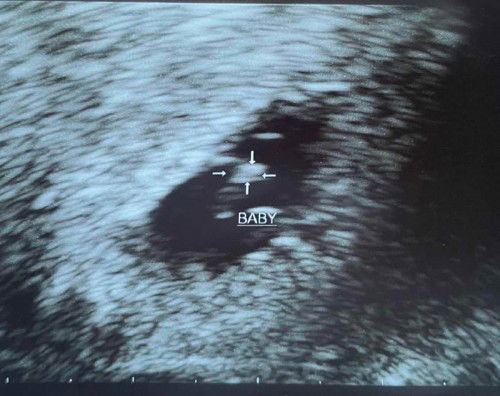

6weeks after IVF/FET scan show baby 5wk+

Second scan after 6week passed FET. Last scan 2weeks ago seen yolk sac only. Today scan show baby with heart beat. But still say it’s about 5week+ and slow heart beat. I was still put in risky stage and asked to come back two weeks later. Dr say there’s nothing much I can do. Just wait for next scan to see improvement. This is my first pregnancy. So anxious. Is any mummy experience before? Any tips for healthy baby growth? My calorie intake is about 1400/1500 cal. Now I am thinking to eat more. #firsttimemom #advicepls #firstbaby